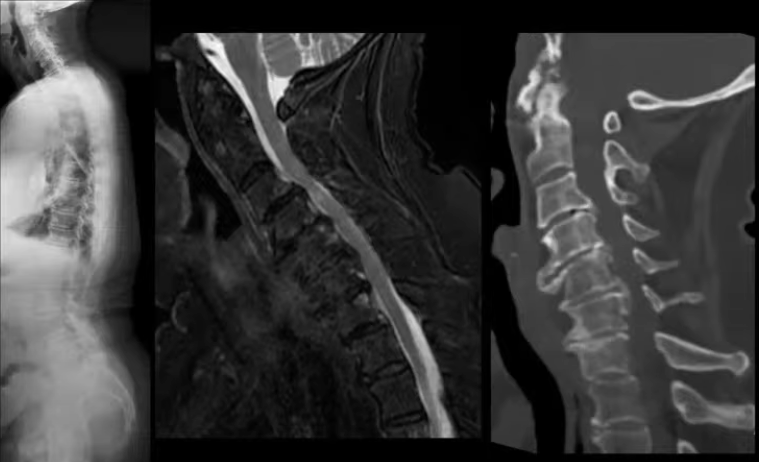

Dive into Interesting Spine Case Discussion, where each session combines brief expert lectures on the latest spine innovations with challenging real-world cases. Learn from fellows and colleagues as you explore both surgical and non-surgical approaches, deepen your clinical insights, and stay current on emerging developments in spine care. Join us to enhance your expertise and elevate your practice.